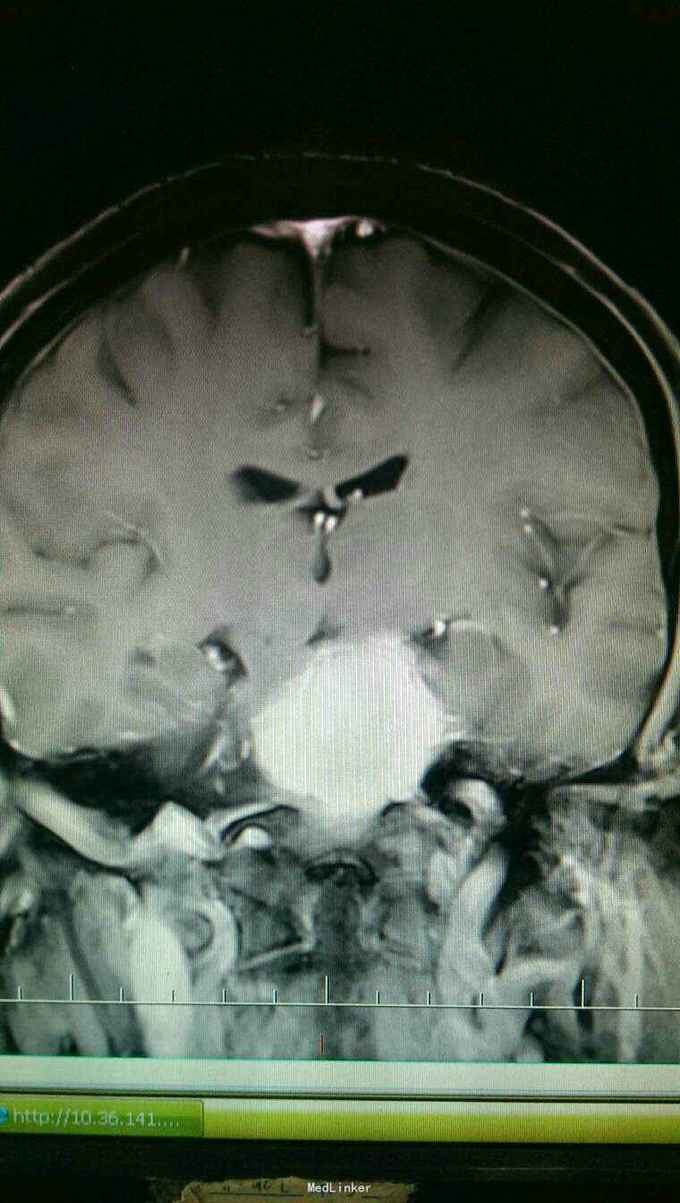

患者以头晕伴走路不稳一个月为主诉入院。患者于入院一个月前自觉头晕,无头痛,无恶心,呕吐。走路不稳,无四肢抽搐及二便失禁。

查体:神志清楚,语言流利。双侧瞳孔等大正圆,直径3.0毫米,光反射灵敏。饮水呛咳,无声音嘶哑。颈软,四肢肌力正常,生理反射存在,病理反射未引出。

入院诊断:岩斜区脑膜瘤。完善术前准备,于全麻下行右侧颞下入路,岩斜区肿瘤切除,术中保留拉贝静脉,剪开小脑幕,近全切除肿瘤。

患者术后病情稳定,岩斜区位于颞骨岩部背面与枕骨斜坡部的岩斜裂汇合处,从岩骨尖至颈静脉孔。内侧至斜坡中线,外侧至第Ⅴ、Ⅶ和Ⅷ脑神经,上缘为鞍背,下缘为颈静脉孔水平;下方为枕骨大孔区。岩斜区脑膜瘤由于位置深,毗邻重要解剖结构,很难实现肿瘤全切除,且有较高的术后致残率,一直是神经外科手术的治疗难点。颅内脑膜瘤约0.3%~1.0%起源于岩斜区,是岩斜区最常见病变。它向上可侵犯岩骨尖、小脑幕、Meckel腔、鞍旁和海绵窦;向下侵犯内听道和颈静脉孔;向内侧达脑干和椎-基底动脉。当肿瘤很大时,可包绕同侧Ⅲ~Ⅺ脑神经。患者临床可表现头痛、复杂的脑神经麻痹、共济失调等症状,严重者表现为偏瘫、认知功能障碍。岩斜区脑膜瘤多数表现良性过程,目前,仍以手术切除为首选治疗方式。 岩斜区脑膜瘤手术技术非常关键,需要熟悉岩斜区解剖关系并有丰富的显微操作经验。在术前放置腰穿引流,或术中甘露醇应用可明显降低脑组织压力,减少牵拉造成的副损伤。提前对脑膜瘤基底的处理可有效避免肿瘤持续出血造成的蛛网膜界面消失。肿瘤的生长将神经、血管拉伸或包绕,尤其是复发的肿瘤,会破坏蛛网膜界面,侵犯脑干软脑膜。手术时应仔细分辨和保护。肿瘤囊壁与神经、血管外膜和脑干粘连,不应勉强分离,以保护下方结构。 待术后平稳复查头Ct。